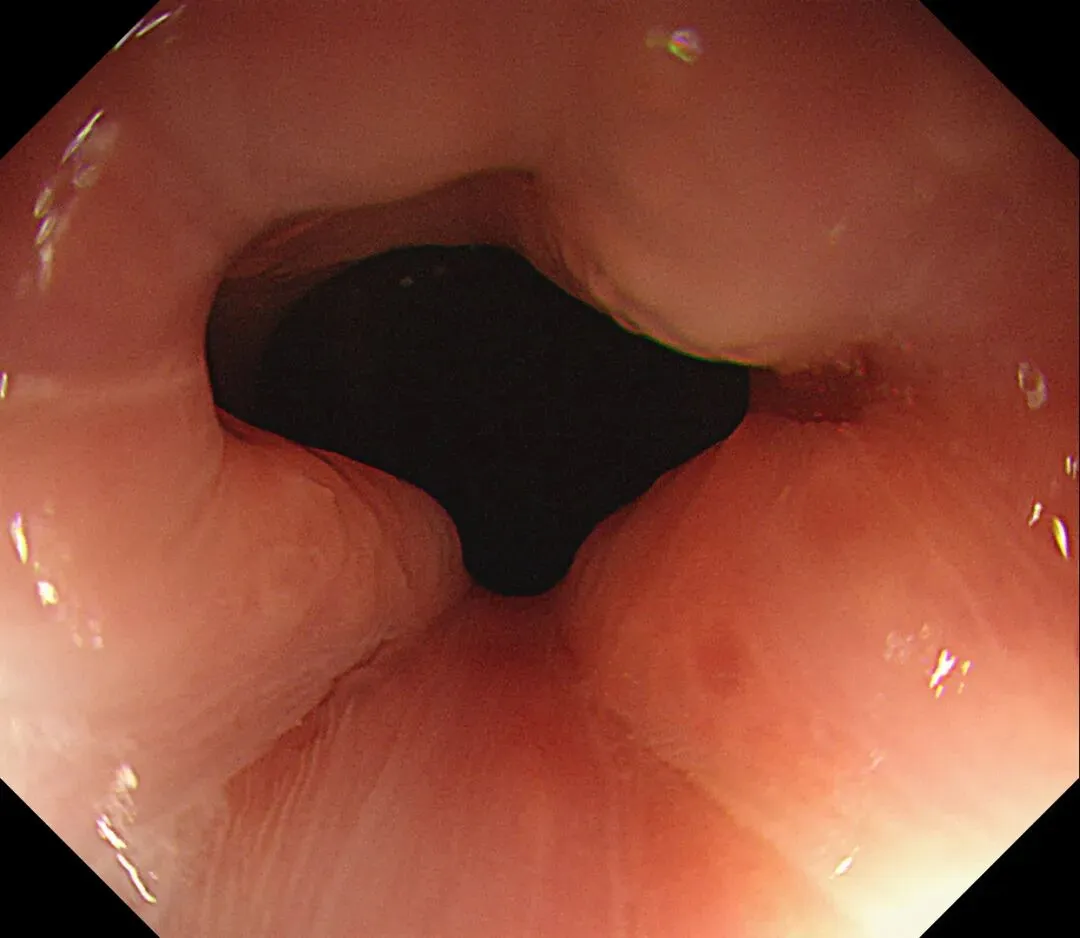

进镜至贲门观察到“花环征”,提示存在AIG的可能,带学生的内镜老师这个moment可以装一把,不过。。。偶尔也有翻车的时候,以下这例是在“Hp现症感染C3萎缩”患者的花环

有待进一步研究。。。